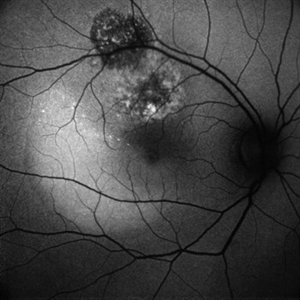

HEALED MULTIFOCAL CHOROIDITIS

COLOUR FUNDUS PHOTO OF A 32 YEAR OLD FEMALE WITH HEALED MULTIFOCAL CHOROIDITIS

Photographer: Dr. Akansha Sharma-Retina Foundation, Ahmedabad

Condition/keywords: multifocal choroiditis